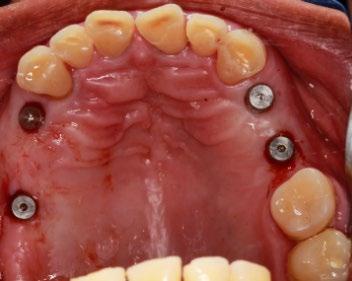

Figura 5. Primera fase quirúrgica de implantes dentales y segunda fase quirúrgica de colocación de tornillos de cicatrización en la zona de los O.D. 16, 15, 24, 26, 36, 32, 42, 46 y 47.

Se montaron los modelos de estudio en un articulador semiajustable Axiomath, aumentando 0.4 mm de DV. Con base en esto, se realizó el encerado diagnóstico (Figura 3). En la fase preventiva, se llevó a cabo una profilaxis con ultrasonido. Posteriormente, se realizaron extracciones de piezas dentarias con mal pronóstico. Se elaboró una guía de silicona basada en el encerado diagnóstico para el mock-up,

En la primera fase quirúrgica se colocaron los implantes dentales en las zonas de las piezas 16, 15, 24, 26, 36, 32, 42, 46 y 47. A los 6 meses se evaluó la osteointegración hueso-implante, y

Figura 6. Desgaste de los O.D. 17, 13, 12, 11, 21, 22, 23, 37, 35, 34, 33, 43, 44 y 45 para prótesis fijas estéticas.

posteriormente se procedió a la segunda fase quirúrgica con la colocación de tornillos de cicatrización (Figura 5). En la fase protésica, se procedió al desgaste de las piezas para las prótesis fijas (Figura 6), se tomaron impresiones a 2 pasos con doble hilo retractor, y se enviaron al laboratorio dental para la elaboración de coronas de E-max. Mientras tanto, se colocaron restauraciones provisionales. Posteriormente, tras el cementado de las restauraciones definitivas (Figura 7), se procedió a la rehabilitación sobre implantes. Se tomaron impresiones a cucharilla abierta, que se enviaron al laboratorio para la elaboración de coronas sobre implante. Se realizó la prueba de biscocho, analizando la oclusión, y luego se reenviaron al laboratorio.

Finalmente, al recibir las coronas sobre implantes, se fijaron las restauraciones con un torque de 25 newtons, dejando las piezas sobre implantes en desoclusión (Figura 8).